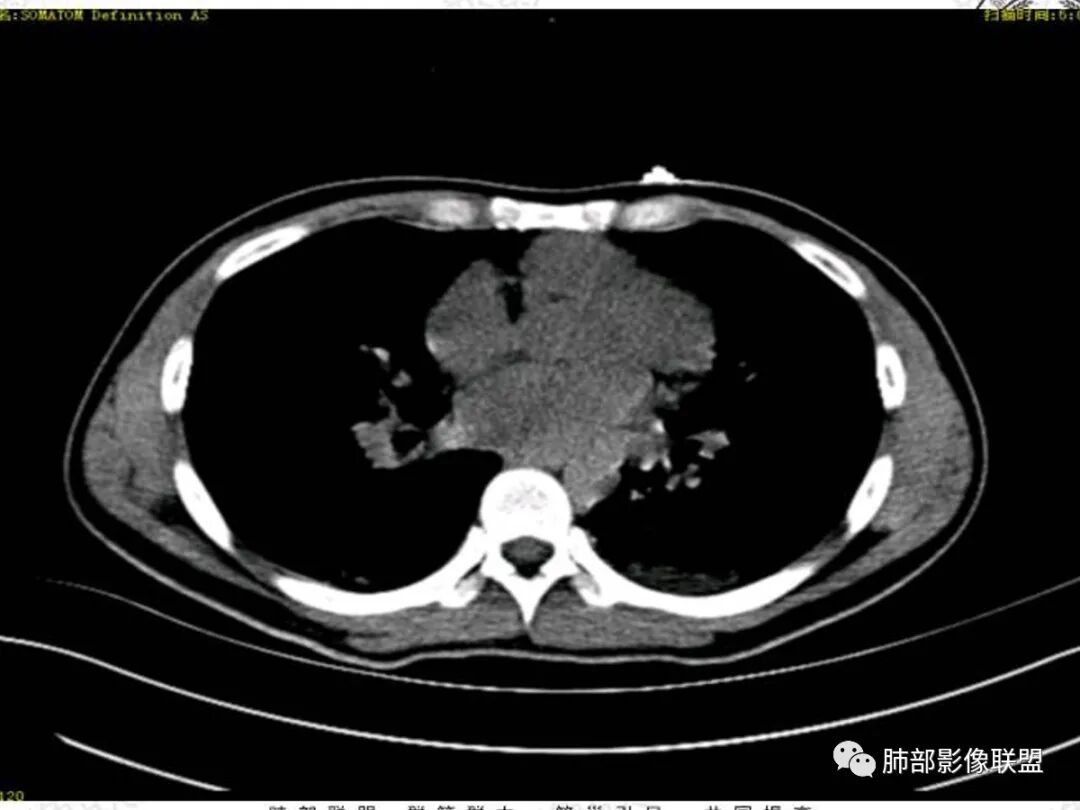

青年男性患者,气促7小时入院,白细胞及中性粒明显增高,PCT增高,CRP不高,心率快,呼吸急促,意识模糊,低氧血症,I型呼吸衰竭,PH偏低,失代偿性酸中毒,BNP偏高,胸部CT:双肺弥漫性多发斑片状实变密度影,双上肺明显,间质改变为主,综合:年轻男性,急性起病,迅速恶化,考虑中毒可能,鉴别:PCP,过敏,

双肺叶透亮度对称性减低,呈磨砂状,小叶间隔规则增厚,上叶为甚,左右肺叶中轴间质增厚(示淋巴回流障碍),双肺叶弥散磨GGO征,以肺腺泡分布,双肺上,下叶融合片状,有重力分布特点,心脏大,肺动脉干增粗,首选心源性肺水肿,但无胸腔积液。与急性肺损伤和ARDS鉴别

青年男性,气促7小时入院,意识模糊,白细胞及中性粒明显增高,PCT增高,CRP不高,心率快,体温正常,血压正常。胸部CT:双肺上叶小叶间隔光滑增厚,中轴间质增厚,弥漫性磨玻璃、多发斑片影,以上肺、背侧分布为主。影像表现考虑为肺水肿。病因:病史不支持肾功能衰竭、心源性、高原性肺水肿,无发热,似乎也不支持细菌、病毒、真菌等感染引起。吸入毒物?吸入水?

肺水肿应该没啥疑问吧,就是病因的问题吧

对称性小叶间隔增厚

高密度影重力趋势

病灶的分布以上肺为主

确实要考虑吸入,倾向于吸入的是气体类的可能,因为朝上走

结合病史,最终诊断是 “急性烟雾吸入性肺损伤”,影像学表现主要是肺水肿及弥漫性肺泡损伤改变,因为烟雾气体吸入肺内分布以上肺显著,因此影像学表现也是累及上肺更明显。损伤因素包括大量一氧化碳 二氧化碳 一氧化氮等燃烧产生的有毒气体,也有烟雾粉尘颗粒对气道黏膜的损伤。